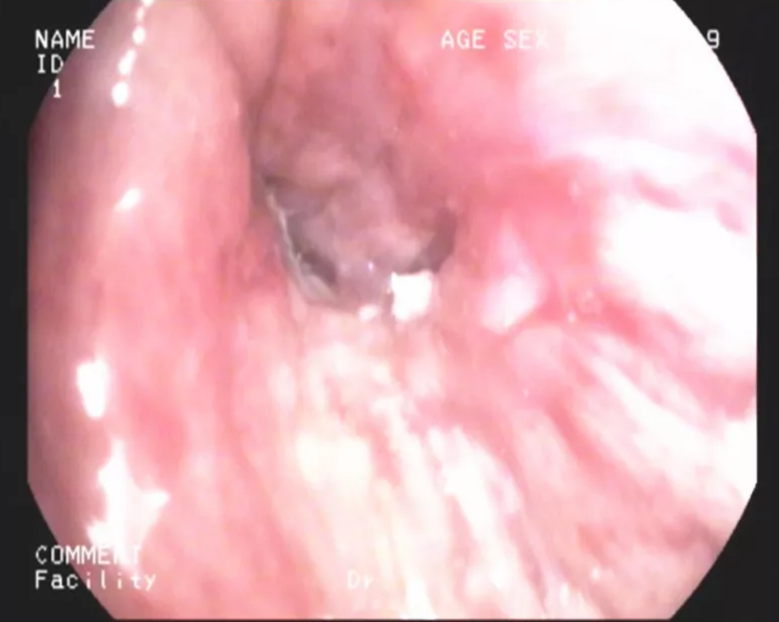

治療中

光動(dòng)力治療( PDT, Photodynamic therapy) ,是一種有氧分子參與的伴隨生物效應(yīng)的光敏化反應(yīng),其過(guò)程特定波長(zhǎng)的激光照射使組織吸收的光敏劑受到激發(fā),氧分子通過(guò)能量傳遞,產(chǎn)生自由基和單態(tài)氧等活性氧,產(chǎn)生細(xì)胞毒性作用,從而導(dǎo)致腫瘤細(xì)胞受損,腫瘤組織凋亡。